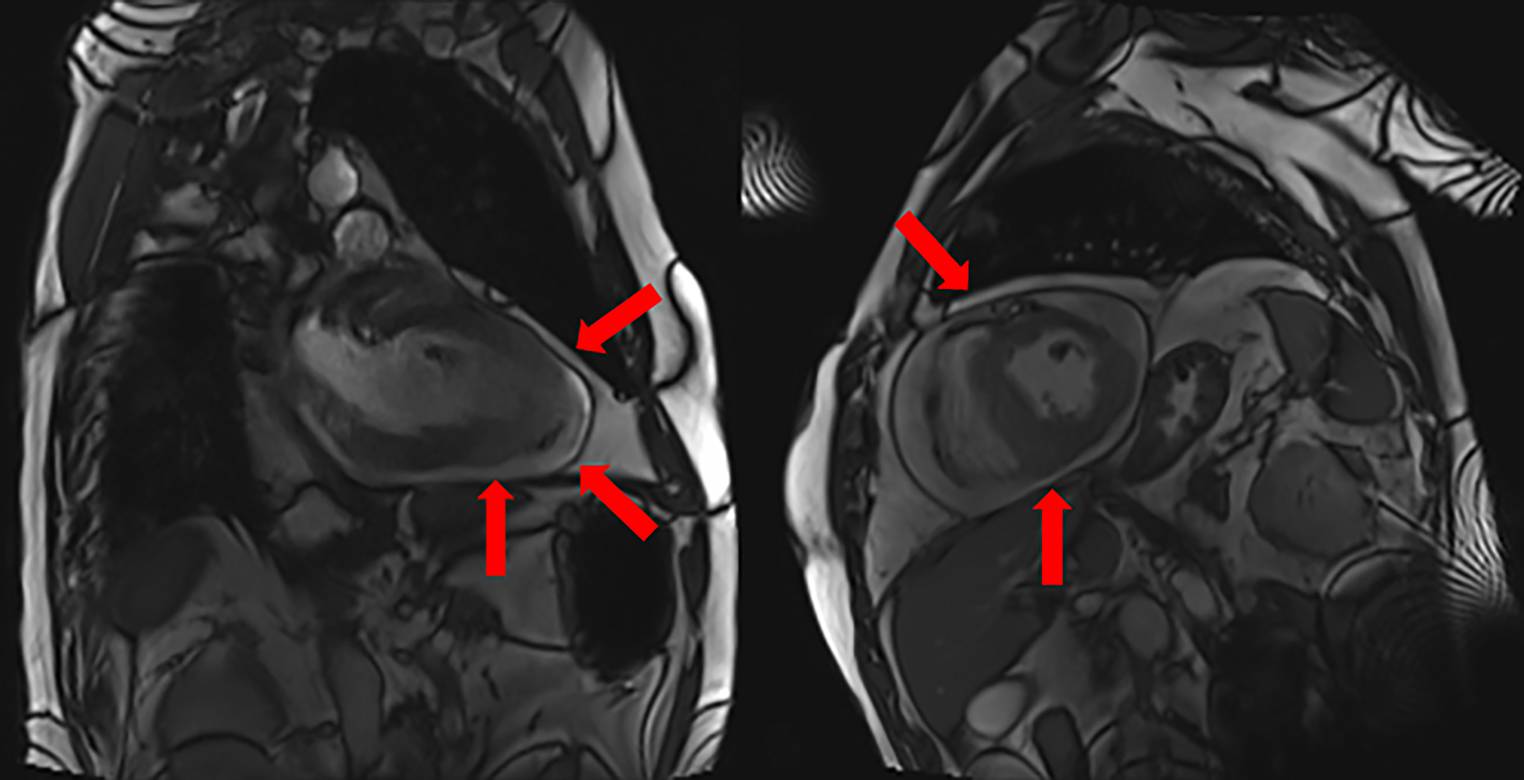

Fig. 2

Magnetic resonance imaging showing Diffuse large B-cell lymphoma (DLBC) infiltration of the left ventricular myocardium with epifocal edema (red arrows)

A 61-year-old man was admitted to the emergency department with fatigue and bilateral leg edema. The patient had been diagnosed with a primary testicular diffuse large B cell lymphoma 1 year previously. He had undergone chemotherapy according to the R‑CHOP 21 protocol and had additionally received three cycles of high-dose methotrexate for central nervous system (CNS) prophylaxis. First complete remission (CR) was achieved after four cycles of R‑CHOP 21. Physical examination revealed wet breath sounds as well as massive bilateral leg edema. Laboratory findings showed high pro-BNP (19,500 [0–100 pg/ml]) and elevated high-sensitive troponin T (123 [0–14 pg/µl]). Cardiac ultrasound demonstrated pericardial effusion (3 cm end-diastolic) and paradox septum movement as well as solid formations swinging in the effusion. During ongoing examination, the patient became unconscious and suffered cardiac arrest. Immediate cardiopulmonary reanimation was initiated. Ventricular fibrillation was documented by 12-channel electrocardiography (Fig. 1). After 10 min of resuscitation and defibrillation, the patient achieved return of spontaneous circulation (ROSC). After stabilization of his vital signs, cardiac MRI was performed, revealing myocardial infiltration of the left ventricle most likely due to lymphomatous formations (Fig. 2). Due to myocardial location and reduced patient performance score, biopsy could not be performed. Dexamethasone with a dose of 40 mg/day was administered as the first step of lymphoma salvage treatment. The PET imaging confirmed the MRI finding of cardiac relapse, with high tracer uptake in the whole myocardium as well as involvement of mediastinal lymph nodes. For prevention of further life-threatening arrhythmias and sudden cardiac death, the patient was equipped with a WCD. Within the course of relapse, the patient developed acute renal failure. This fact disqualifies him from standard platinum-containing salvage therapy. Therefore, pixantrone combined with rituximab and dexamethasone was used, leading to disappearance of cardiac effusion and improvement of cardiac function as well as partial response of the DLBCL, with remaining 18-fludeoxyglucose uptake in mediastinal lymph nodes. After commencement of pixantrone plus rituximab, no further life-threatening arrhythmia were observed. Unfortunately, the patient developed a third, refractory mediastinal relapse of his lymphoma and died 10 weeks after diagnosis of his cardiac relapse.